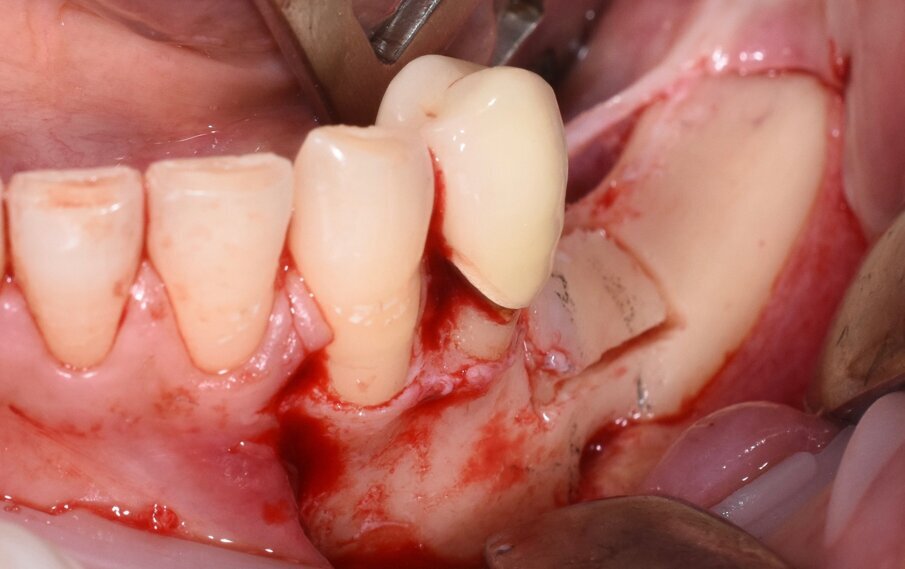

Considerata la necessità di eseguire un riabilitazione implantoprotesica della sede edentula si è resa necessaria l’avulsione dell’elemento incluso con tecnica piezoelettrica che ci ha permesso di ridurre al minimo l’osteotomia e preservare l’integrità del nervo la cui emergenza si trovava esattamente in corrispondenza della corona del 3.5 (Figg. 3-9).

Fig. 9 - Rimozione della corona.

Fig. 10 - Cavità alveolare residua che evidenzia l’integrità del nervo mentoniero.